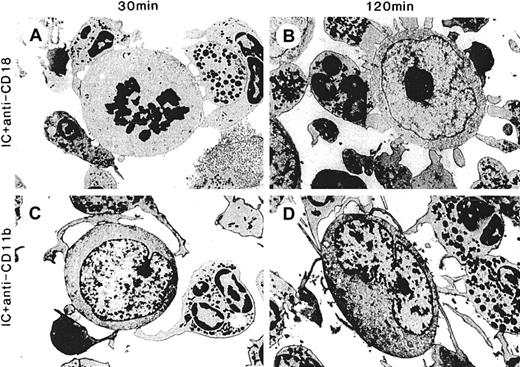

Spreading and adhesion by PMN on target cells and cytolysis is greatest with hu14.18/GM-CSF and requires Mac-1

Effect of function-blocking mAbs against Mac-1 (CD11b/CD18) on spreading, adhesion, and cytolysis by PMN with hu14.18/GM-CSF.

ADCC with hu14.18/GM-CSF was as described in Figure 3 except that function-blocking mAbs were added just before the addition of hu14.18/GM-CSF. ADCC was performed in the presence of anti-CD18 7E4mAb (10 μg/mL) for (A) 30 minutes and (B) 120 minutes or anti-CD11b 2LPM19C mAb (10 μg/mL) for (C) 30 minutes and (D) 120 minutes. Electron micrographs were taken with an original magnification of × 5400.